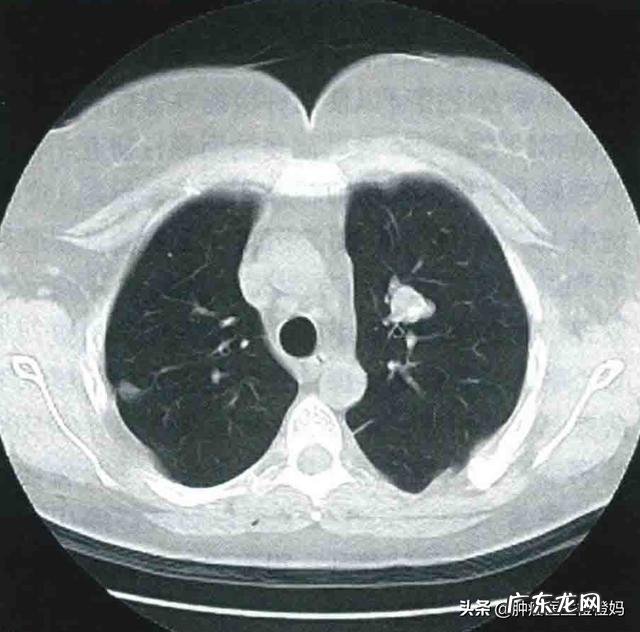

鼻咽癌最常见的骨转移部位为椎体转移,就是后背正中的骨头,患者常给我描述为“龙骨” 。骨转移初期往往没有任何症状,我之前就有病人定期复查时发现EBV-DNA明显偏高,达到50000多,胸腹部CT显示多发椎体转移,患者本人是没有任何异常表现的 。如果有症状了,最明显的表现就是骨痛,初期为隐痛,后逐渐加重,如果在椎体骨转移,弯腰活动时骨痛往往会加重 。(3)肺转移